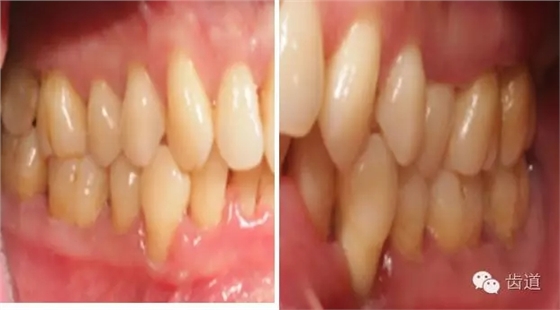

1、口腔衛(wèi)生狀況及局部刺激物(牙菌斑、牙石,不良修復(fù)體)

牙石及不良修復(fù)體

2、牙齦

(顏色、形狀、質(zhì)地、退縮、BOP、PD、附著齦)